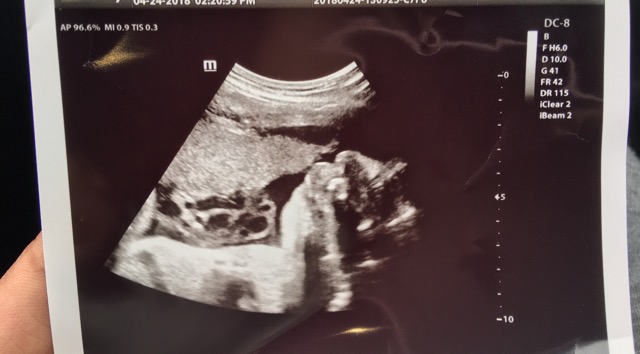

Baby Covering Face In Ultrasound

In this 3D image the baby-to-be is curled up her hands covering her face shes about the size of a grapefruit.

Covering part of the. Ultrasounds show fetuses covering their face and touching their mouth more often if their mothers smoke while pregnant medical journal study. Seeing your unborn child for the first time is sure to touch your heart.

How much you see of your baby during the 3D ultrasound will really depend on the way they are laying.